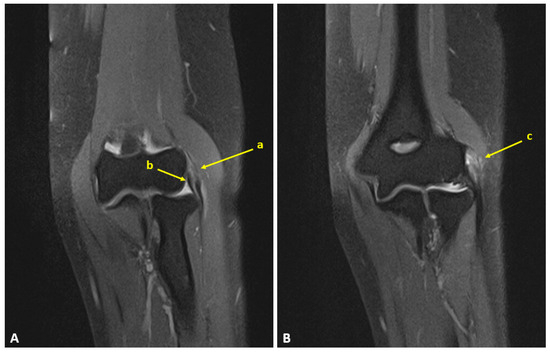

A Novel Modification of Anconeus Muscle Flap for Extensor Digitorum Communis-Selective Lateral Epicondylitis: Preliminary Clinical Study

Introduction: Lateral epicondylitis (LE) typically affects the extensor carpi radialis brevis (ECRB) tendon, while isolated degeneration of the extensor digitorum communis (EDC) origin is rare and poorly characterized. Surgical debridement of these lesions may result in capsular exposure requiring soft-tissue coverage, which can be achieved through a vascularized muscle flap to enhance tendon healing potential and reduce recurrence. This study aimed to describe a modification of the anconeus rotation flap as originally described by Almquist in 1998, and to evaluate its clinical and functional outcomes in patients with isolated EDC tendinopathy. The modified technique consists of a simpler muscle advancement (AMA) that preserves the distal vascular pedicle and reduces soft-tissue dissection. Methods: A retrospective study was conducted on 12 consecutive patients with lateral epicondylitis with isolated EDC tendon involvement (10.71% of all operative cases at our Institution between 2019 and 2022), who were surgically treated with the anconeus muscle advancement modification. Clinical outcomes, including the visual analog pain scale (VAS), grip strength and patient-reported outcome measures (PROMs), which include the QuickDASH score, the Mayo Elbow Performance Score (MEPS) and the Patient-Rated Tennis Elbow Evaluation (PRTEE) score were assessed. Paired statistical tests with 95% confidence intervals and minimal clinically important difference (MCID) thresholds were applied. Results: At a mean follow-up of 38 months, all outcomes demonstrated statistically significant and clinically meaningful improvements (p < 0.05). Reductions in pain/disability (VAS, QuickDASH, PRTEE scores) and functional gains (Grip strength, MEPS) far exceeded their respective MCID thresholds, with 100% attainment for each outcome. Conclusions: This modified anconeus muscle advancement appears to be a technically feasible option for managing isolated EDC-related lateral epicondylitis, preserving vascular integrity while limiting dissection. Although favorable results were obtained, the small retrospective cohort precludes definitive conclusions regarding efficacy. The findings support the technical feasibility of the proposed modification and warrant further prospective comparative investigations.